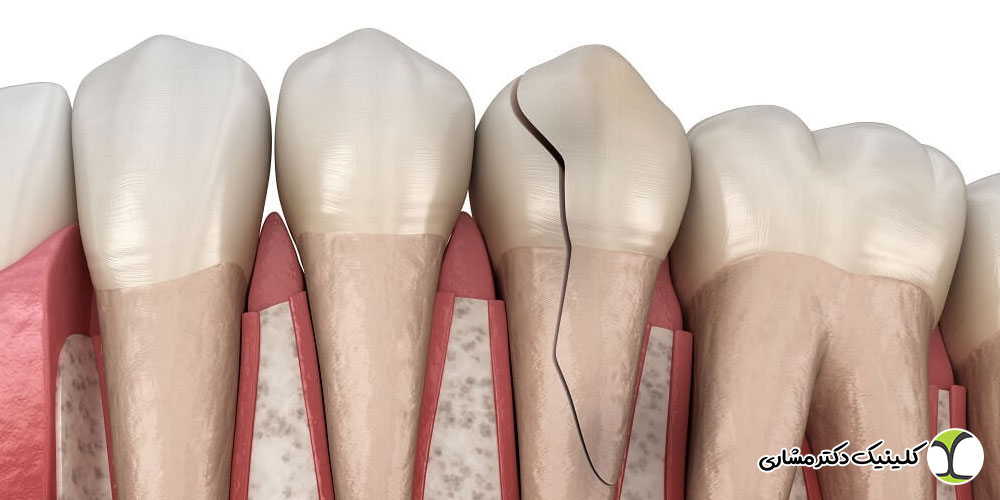

- ایمپلنت باید کاملاً ثابت باشد. اگر هرگونه حرکت، تکان خوردن یا احساس شل شدن داشتید، احتمال شکست کاشت وجود دارد.